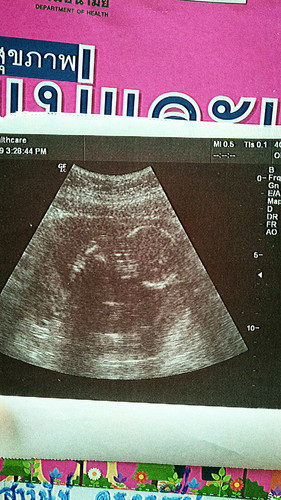

16วีคดูยังไงค่ะ

บ้านนี้ดูไม่ออกเลย เห้นแต่กลมๆคือหัวน้องใช่ไหมค่ะ หมอไม่ได้บอกอะไรเลย

ซาวด์ที่ รพ.หรอคะ ไม่แน่ใจว่าใช่หัวใหม ไม่ชัด